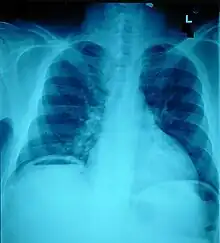

Pneumoperitoneum, seen as an air bubble on the lower left side of the X-ray film

Ten percent of people with polytrauma who had no signs of abdominal injury did have evidence of such injuries using radiological imaging.[1] Diagnostic techniques used include CT scanning, ultrasound,[1] and X-ray.[7] X-ray can help determine the path of a penetrating object and locate any foreign matter left in the wound, but may not be helpful in blunt trauma.[7] Diagnostic laparoscopy or exploratory laparotomy may also be performed if other diagnostic methods do not yield conclusive results.[5]